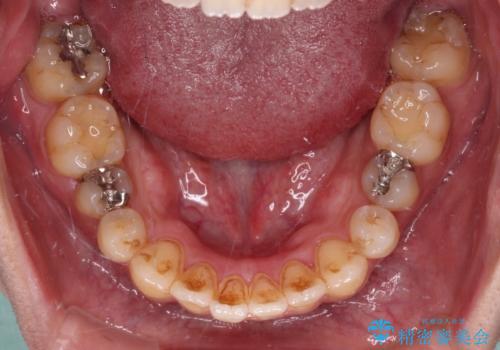

オープンバイトと目立つ銀歯 インビザライン矯正とセラミック修復治療

- 奥歯の目立つ銀歯と上下前歯の叢生と隙間を気にして来院された患者様です。

開咬の治療は、前歯を閉じるように動かすとともに、上下臼歯を圧下(骨内にめり込ませる)させることで進めて行きます。

インビザラインは臼歯の圧下を効果的に行えるため、インビザラインを用いて矯正治療を行うこととしました。

銀歯については、矯正治療により咬合関係を改善し、矯正治療後半に修復治療を行うこととしました。

修復治療後に細かい部分をインビザラインで再度仕上げるプランとしました。

銀歯のセラミック治療が1番の希望であったため、ここまで歯列がきれいに整うとは思ってなかったようで、大変喜んでいただけました。